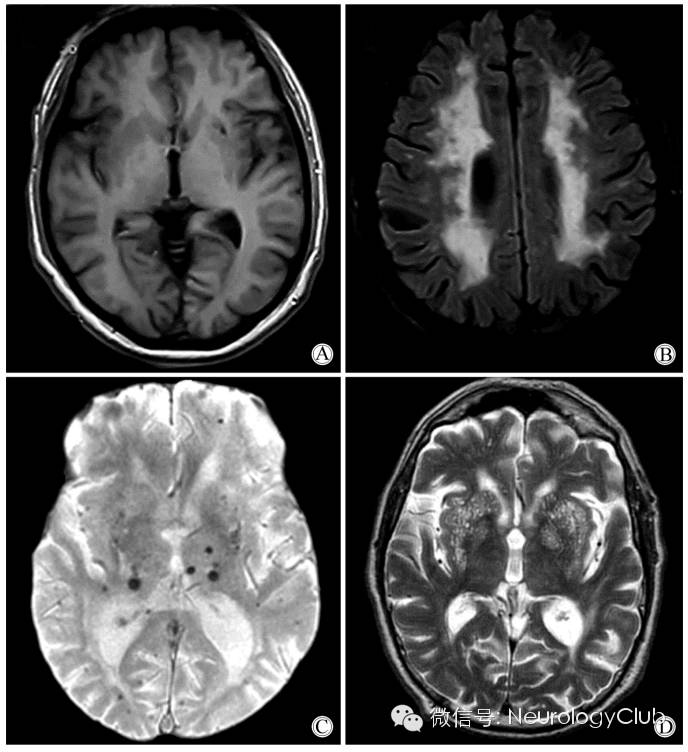

(CSVD的重要影像学特征。A:DWI提示急性深部小梗死[腔隙性梗死],直径<2cm;B:FLAIR上提示腔隙,内为脑脊液,直径在3mm-1.5cm之间,位于白质或深部灰质或者脑干,信号同脑脊液;C:FLAIR提示白质高信号,见于白质和深部灰质以及脑干,呈T2/FLAIR高信号,T1WI多不可见但偶为低信号,数量较多时可融合;D:T2WI提示血管周围间隙,因内为脑脊液样液体故而呈高信号,直径<3mm,圆形或线形,位于白质和深部灰质,明显时T1上可见低信号)

(A:T1WI腔隙灶;B:FLAIR脑白质 病变;C:T2*WI微出血;D:T2WI扩大的血管周围间隙)